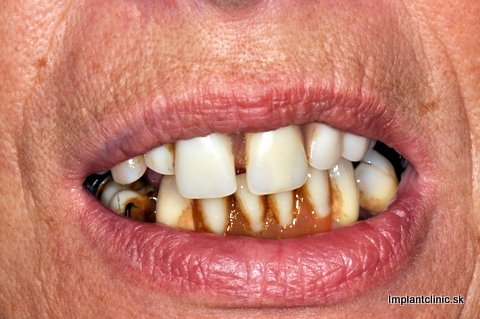

Takto sa vyjadrila o Implant Clinic Vendy. Podstúpila zákrok, ktorý vyžadoval dvojitú dostavbu kosti, 10 zubných implantátov a 24 implantátových koruniek. Ak zuby chýbajú dlhšiu dobu môže dojsť k úbytku kosti. Resorpciou kosti strácajú mäkké tkanivá oporu, čím môže Vaša tvár nadobudúť starší vzhľad.

Umiestnením zubných implantátov do čeľustnej kosti predchádzame tomuto procesu, pretože podobne ako Vaše vlastné zuby aj zubné implantáty prenášajú žuvacie sily na okolitú kosť, čo ju stimuluje a tým sa predchádza úbytku kosti. V niektorých prípadoch ako u Vendy bola potrebná dostavba kosti. Mnoho ľudí má mýlnu mienku o tomto zákroku a myslia si, že je to zložitý proces.